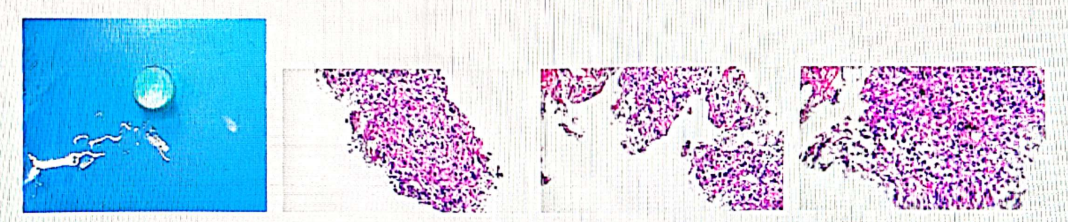

病理相关检查:

2023-11-23病理示(肺穿刺活检)结合形态及免疫组化结果,符合非小细胞肺癌,分型倾向腺癌。

免疫组化结果:TTF-1(部分弱+),CK7(+),Brg 1/SMARCA4(+),Napsin A(-),CK5/6(-),P40(-),PD-L1(TPS:75%),Neg Ctrl(PD-L1)(-),Ki-67(约35%+)。

特殊染色:AB-PAS(-)